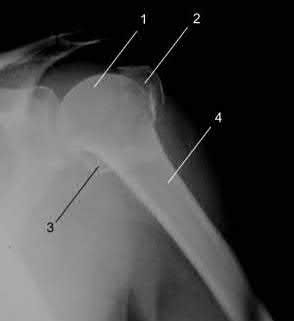

A 70-year-old woman falls down a flight of stairs and sustains the injury shown in Figures A and B to her dominant upper extremity. She lives alone and has no other medical history. Which of the following surgical options is best to minimize complications for this fracture pattern?

This patient has a complex proximal humerus fracture with metaphyseal comminution and poor bone stock. Cemented reverse total shoulder arthroplasty (rTSA) using a long stem prosthesis and tuberosity repair is indicated.

Proximal humerus fragility fractures are hard to treat because of comminution and poor bone stock. AVN is common with glenohumeral fracture-dislocation. Hemiarthroplasty (and standard total shoulder arthroplasty, TSA) is unreliable because of dependence on tuberosity healing. rTSA is recommended for fractures in patients >70 years with severely comminuted fractures, high likelihood of head AVN, and poor tuberosity bone quality (osteoporosis or comminution).

Figures A and B are AP radiograph and 3D reformatted CT scan showing comminuted proximal humerus fracture dislocation. Illustration A shows rTSA performed with distal cementation of a long stem prosthesis and cerclage fixation of the proximal shaft and the tuberosity fragments.